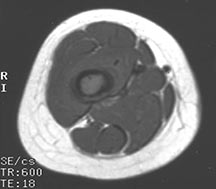

- May arise from any bone and any site within a bone (epiphyseal, metaphyseal, diaphyseal)

- Radiographically variable appearance: may appear benign (geographic) or malignant (permeative or moth eaten)

Radiographic Presentation